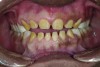

The authors report on a 21-year-old patient who presented with severe discoloration and mild sensitivity of teeth (Figure 1). The teeth visible in his smile were very short, unsightly, and unbecoming for his age.

Figure 1. Preoperative frontal smile of patient suffering from AI, showing small, discolored, worn teeth.

Figure 1